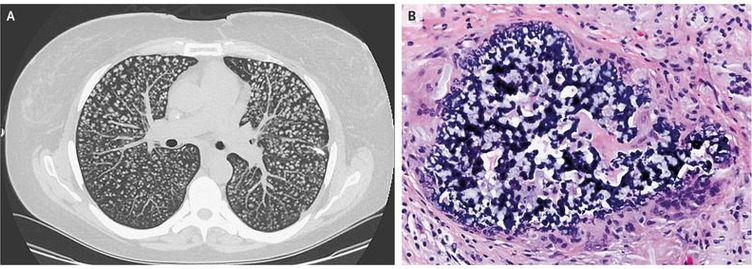

A 31-year-old woman who was receiving long-term total parenteral nutrition after having undergone Roux-en-Y gastric bypass that was complicated by small-bowel resection presented to the pulmonology clinic with exertional dyspnea that had progressed over the course of 1 year. She had normal oxygen saturation while breathing ambient air and was not in respiratory distress. Breath sounds were normal in all lung fields, with no wheezing, ronchi, or crackles. Computed tomography of the chest revealed diffuse, innumerable centrilobular nodules in both lungs (Panel A). A lung-biopsy sample obtained by video-assisted thoracoscopic wedge resection revealed perivascular aggregates of histiocytes and foreign-body giant cells with abundant basophilic foreign material in coral-like structures (Panel B). The material was confirmed by mucicarmine staining to be crospovidone, an inactive ingredient present in many oral medications. The patient received a diagnosis of pulmonary foreign-body granulomatosis, which can occur after injection or nasal inhalation of pulverized tablets, often opioids or stimulants, that contain inert fillers such as crospovidone, talc, or cellulose. She reported that she had been using the vascular access for her total parenteral nutrition to inject oral opiates that had been previously prescribed for her after abdominal surgery. Although the best available treatment for pulmonary foreign-body granulomatosis has not been established, treatment of the underlying opioid-use disorder is critical. At follow-up 6 months after the patient’s initial presentation (3 months after diagnosis), her dyspnea remained unchanged and was not limiting her daily functioning.